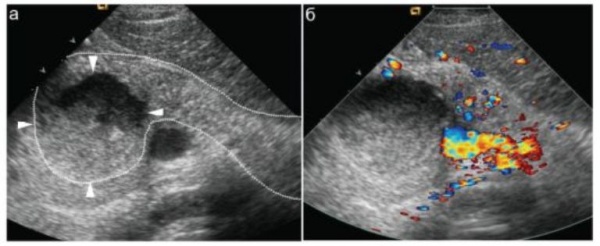

УЗИ поджелудочной железы. На фоне резкого увеличения размеров железы (обведена пунктиром) в ее головке определяется крупный (до 3 см в диаметре) абсцесс (показан стрелками).